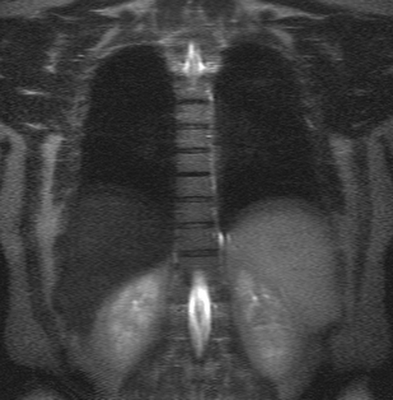

Примеры рентгенограмм, МРТ пояснично-крестцового отдела позвоночника

Грудной отдел позвоночника на МРТ в коронарной проекции